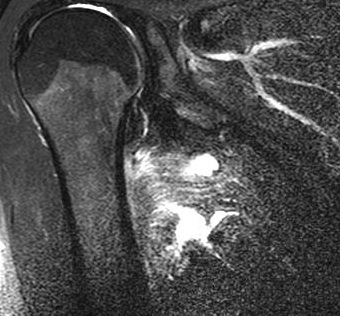

MRI를 통해 부분파열과 완전파열, 급성 손상과 만성 손상의 구별이 가능합니다.

MRI(T2 FS) : 대흉근 파열(Pectoralis major rupture)